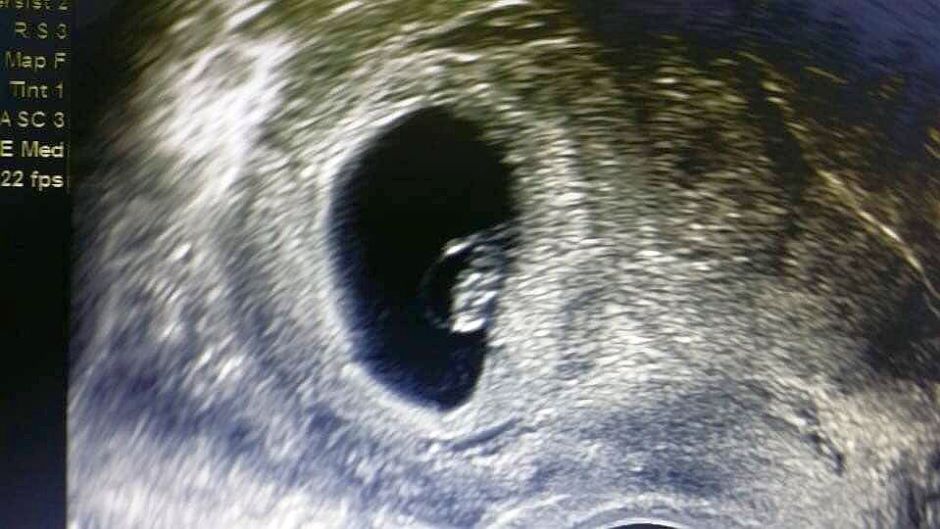

PETALING JAYA: Isteri kepada pelakon Fizo Omar iaitu Mawar akhirnya disahkan hamil beberapa minggu selepas empat tahun berumah tangga.

Berita gembira itu diumumkan oleh Pakar Perbidanan dan Sakit Puan, Dr. Hamid Arshat.

Katanya, Mawar hamil selepas menjalani beberapa pembedahan dan mendapat beberapa rawatan susulan.

"Setelah menjalani pembedahan dan berbagai rawatan susulan akhirnya dengan izin dan rahmat Allah SWT Mawar hamil.

"Sekarang dalam peringkat awal kehamilan. Dalam keadaan biasa, risiko gugur sebelum 12 minggu kehamilan adalah dalam lingkungan 10 peratus.

"Risiko ini meningkat bagi mereka yang mengalami masalah kesuburan dan khususnya yang menjalani pembedahan pada peranakannya," tulis pakar perubatan itu di laman sosial Facebook miliknya.